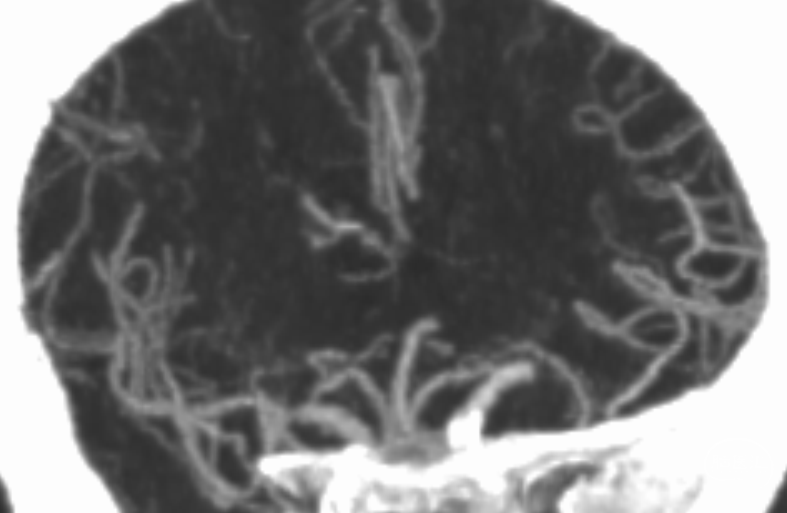

动脉晚期冠状位脑膜支逆流

动脉晚期矢状位脑膜支逆流

CTA

多模式影像学评估可协助血管闭塞性质的判断,特别是多时相CTA扫描;